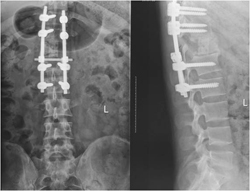

下面这个病人是个25岁的青年男性,因为下肢无力在当地医院就诊,发现T12肿瘤压迫脊髓。为了挽救神经功能,当地医生给病人做了后路椎板切除减压,椎体内肿瘤刮除及椎弓根螺钉固定手术。术后肿瘤的病理结果回报为骨巨细胞瘤。虽然神经功能改善明显,步行出院,但1年半之后肿瘤复发,不仅再次压迫脊髓而且肿瘤蔓延到相邻的3节脊椎。

图1-2,术后X片显示当地医院行后路T12附件切除减压,经椎弓根椎体肿瘤切除,T11-L1椎体间异体骨块支撑,T10,11-L1,2椎弓根螺钉固定术。

图1-3,术后1年半CT显示肿瘤复发,累及T11-L1椎体,左侧椎旁肿瘤累及腰大肌从T11蔓延到L2-3椎间盘水平。